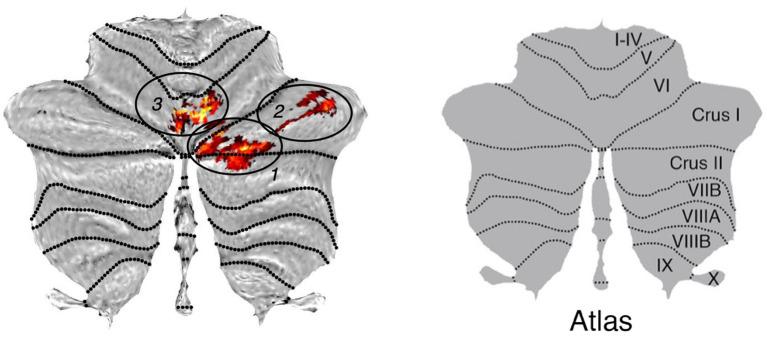

Gray matter (GM) volume loss was found in older participants in three clusters in the right cerebellar region, namely crus I/II and lobule VI related to the frontoparietal network, with crus I being functionally related to the default-mode network and lobule VI extending into vermis VIIa related to the ventral-attention-network.

在老年参与者右侧小脑区域的三个簇中发现灰质体积减少,即与额顶网络相关的 Crus I/II 和小叶 VI,其中 Crus I 在功能上与默认模式网络相关,小叶 VI 延伸至与腹侧注意网络相关的蚓部 VIIa。